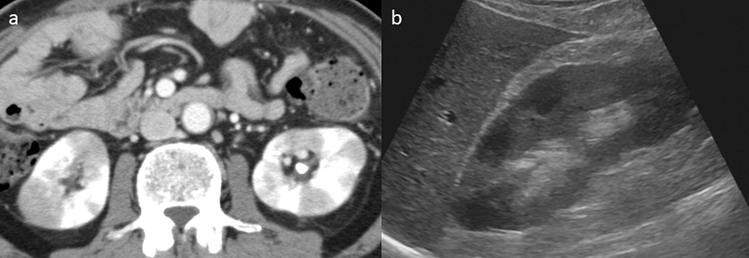

Of the 17 patients in the KD group, 14 (82.4%) had multiple hypodense lesions, 2 (11.8%) had a solitary hypodense lesion, 2 (11.8%) had diffuse thickening of the renal pelvis wall, 1 (5.9%) had diffuse renal swelling on CE-CT, and 2 had multiple findings. All patients underwent transabdominal ultrasound within 1 week after CE-CT; however, abnormalities in the kidneys were detected in only four patients (23.5%) (Fig. 2).

Figure 2.

Comparison of the radiological findings of renal lesions between contrast-enhanced CT and transabdominal ultrasound in a patient with AIP. (a) A contrast-enhanced CT showing multiple hypodense lesions in both kidneys. (b) Transabdominal ultrasound showing multiple ill-defined, non-mass-like areas with decreased echogenicity in the right kidney.